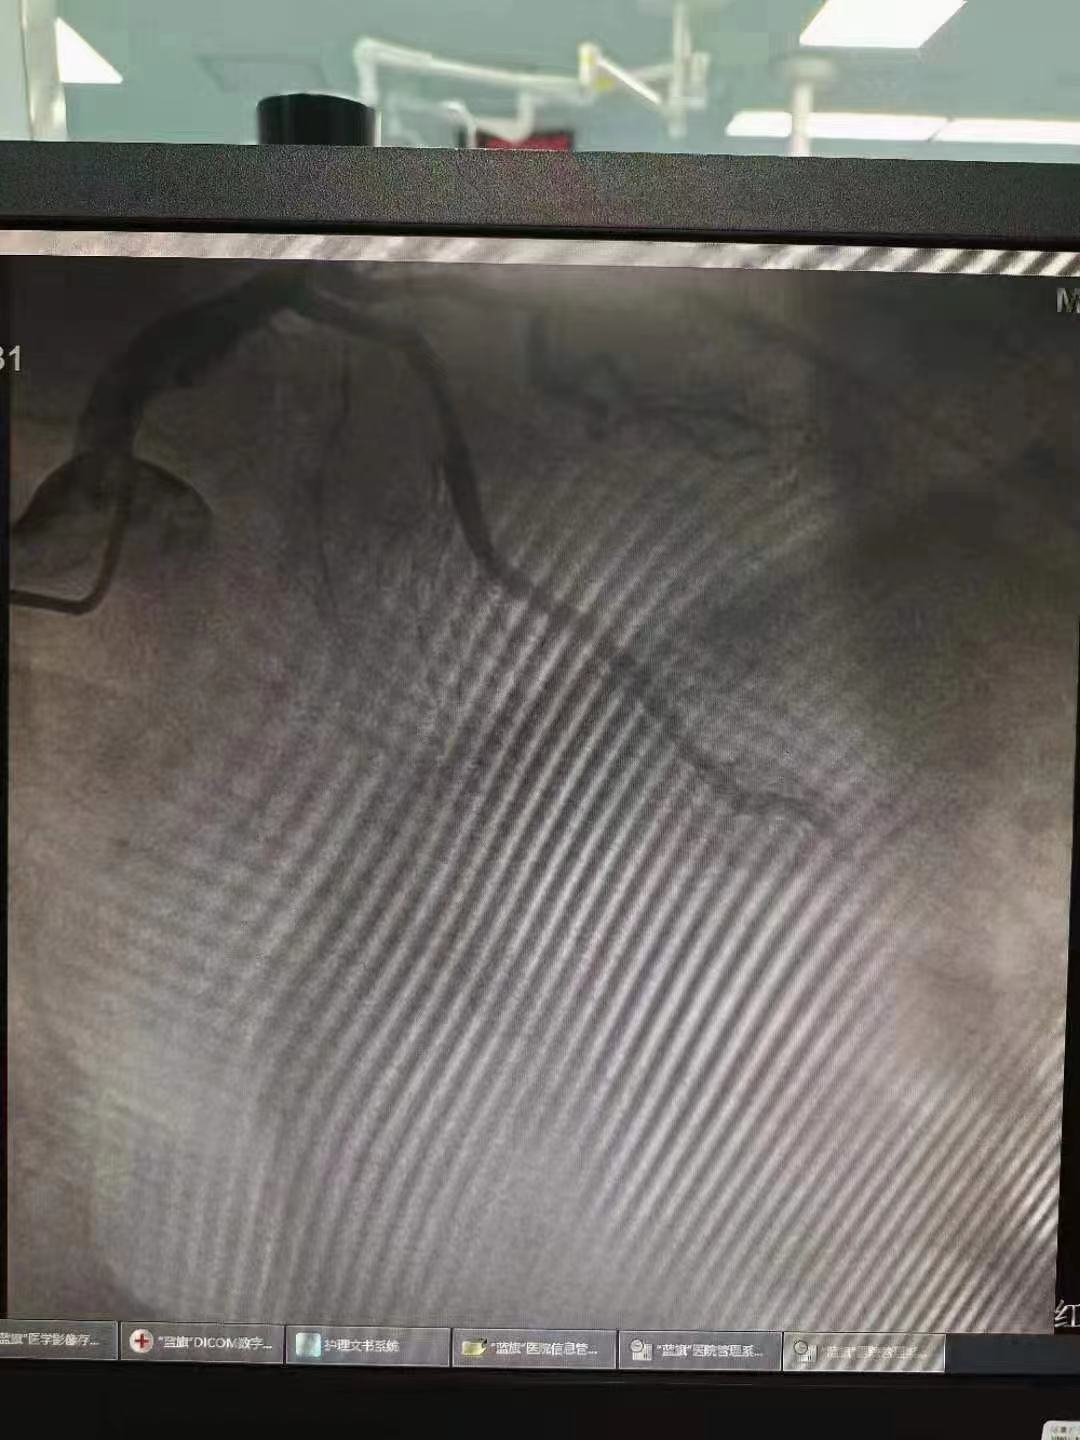

祝賀 云南省滇南中心醫院  黃銳團隊成功為患者植入3.5~15Xinsorb生物可吸收支架!